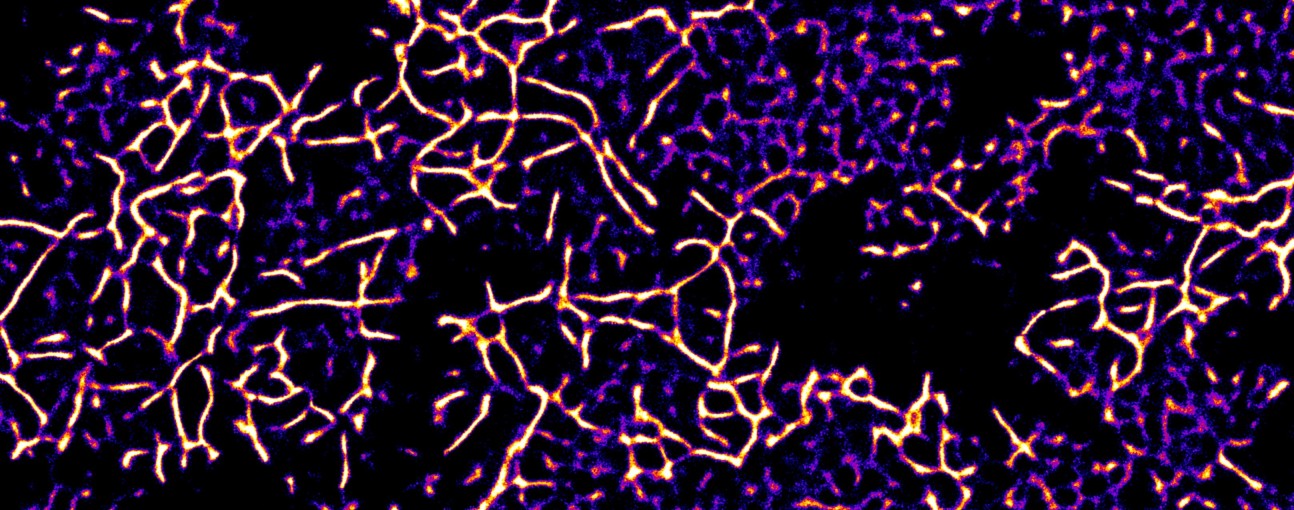

Alpha-synuclein Aggregates - Michael Morton (Research Associate: Ye lab)

"Super-resolved alpha-synuclein aggregates deposited on a glass slide"